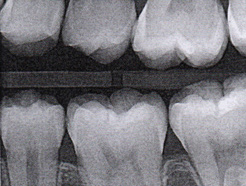

Fig 3. Three thin soft dental picks were used simultaneously for SDF proximal surface saturations in a teenaged patient (Fig 3). After 60 seconds, the treated regions were covered with 5% fluoride varnish (Fig 4). A comparison can be seen of pre-SDF-treatment bitewing films (Fig 5) and 8-month post-SDF bitewing films (Fig 6) for the patient shown in Fig 3 and Fig 4. Radiolucencies were similar or improved, except for contact of maxillary first and second molars.

Fig 5. Three thin soft dental picks were used simultaneously for SDF proximal surface saturations in a teenaged patient (Fig 3). After 60 seconds, the treated regions were covered with 5% fluoride varnish (Fig 4). A comparison can be seen of pre-SDF-treatment bitewing films (Fig 5) and 8-month post-SDF bitewing films (Fig 6) for the patient shown in Fig 3 and Fig 4. Radiolucencies were similar or improved, except for contact of maxillary first and second molars.

Figure 5

Interproximal insertion of SDF is demonstrated in different patients in Figure 3 through Figure 11. Various diameters and brands of soft dental picks may be used depending on the closeness of the proximal surfaces and ease of insertion; for example, some picks are designed for use in wider spaces between teeth. This protocol also offers versatility. Figure 3, for example, shows the simultaneous use of three thin soft dental picks to saturate proximal surfaces with SDF in a teenaged patient; the treated regions were subsequently covered with fluoride varnish (Figure 4). This patient was initially treated in April 2019 (Figure 5), with an identical re-application 3 months later. As shown in Figure 6, the December 2019 bitewing film revealed good results with the possible exception of the contact regions of the maxillary first and second molars. New SDF application was completed in the December appointment.

The senior author's (TPC) private practice experience with soft-tip insertion of SDF into contacting proximal surfaces of teeth is that most beginning proximal surface caries lesions cease to progress, as evidenced by subsequent bitewing radiographic comparisons (Figure 3 through Figure 6, Figure 12 through Figure 18). The chances for success vary, however, depending on frequency of application, subsequent flossing by patients or adults flossing younger children, diet control, individual mouth chemistries, and use of fluorides for the topical effect. It must also be emphasized that office staff should make extensive efforts to inform children and parents that subsequent daily flossing is needed to accompany SDF treatments; otherwise, SDF applications will only delay the inevitable progression of caries. Flossing methods should be demonstrated for patients and for parents so they may see how to floss younger children. Showing them enlarged graphic photographs of flossing results may be helpful in this regard. Parents and patients should be made aware that if interproximal dental plaque accumulations persist without daily interruption by flossing, the acid insult will eventually take its toll on the proximal surfaces and caries lesions will progress to the point where restorative intervention may be required.